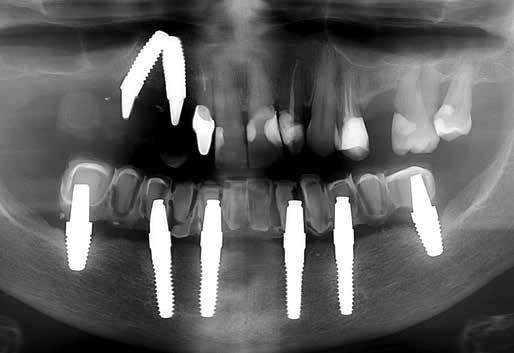

Két év hordás után stabil a helyzet (13. ábra). A töltetlen PEEK radio-transzlucens, a röntgenképen kontúrja csak halványan felismerhető (14. ábra).

13. ábra: Ellenőrzés két év után. 14. ábra: Két év hordás utáni panoráma röntgenkép részlete.

oka az volt, hogy a fogak folyamatosan kitörtek az ötéves pótlásból (9. ábra). Nálunk is mutatkoztak hasonló problémák az ilyen megoldásokkal, ezért mi már nem készítünk ilyet. A megoldást a teljes anatomikus vázzal készülő PEEK hidak jelenthetik, Gradia (GC) kompozittal leplezve, vagy teljes cirkónium-dioxid koronák, mint a bemutatott esetben is (10. ábra). A hölgynél még megvolt a multi-unit analógokkal és ínymaszkkal készült minta, így nem volt szükség új lenyomat vételére. 26 grammos teljes súlyukkal a hidak nagyon könnyűek (11. ábra). Az egyedi cirkonkoronák összeragasztása a PEEK vázzal kiválóan bevált. A direkt a PEEK anyagból kifrézelt multi-unit kapcsolódási felület nem igényli titánkúp beragasztását. Nem tapasztaltunk még csavarlazulást! A multi-unit egységekhez alkalmazott kicsiny csavarok meghúzására ajánlott nyomaték csak 15 Ncm. A teljes cirkonkoronák magas transzlucenciája (12. ábra) a laboratórium folyamatos munkamenete során is biztosítja a jó esztétikai hatást. A koronák egyenkénti elkészítése és rögzítése megőrzi a PEEK váz saját rugalmasságát, így olyan pontosságot biztosít, amely merev hidaknál csak ritkán érhető el. Közvetlenül az új híd becsavarozása után kellemes beszédérzésről számolt be a hölgy, mivel a hidat a PEEK váz következtében gracilisabban alakíthattuk ki.